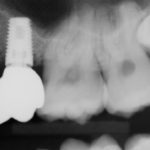

This patient had an Implant placed to replace a missing molar which had been removed due to infection.